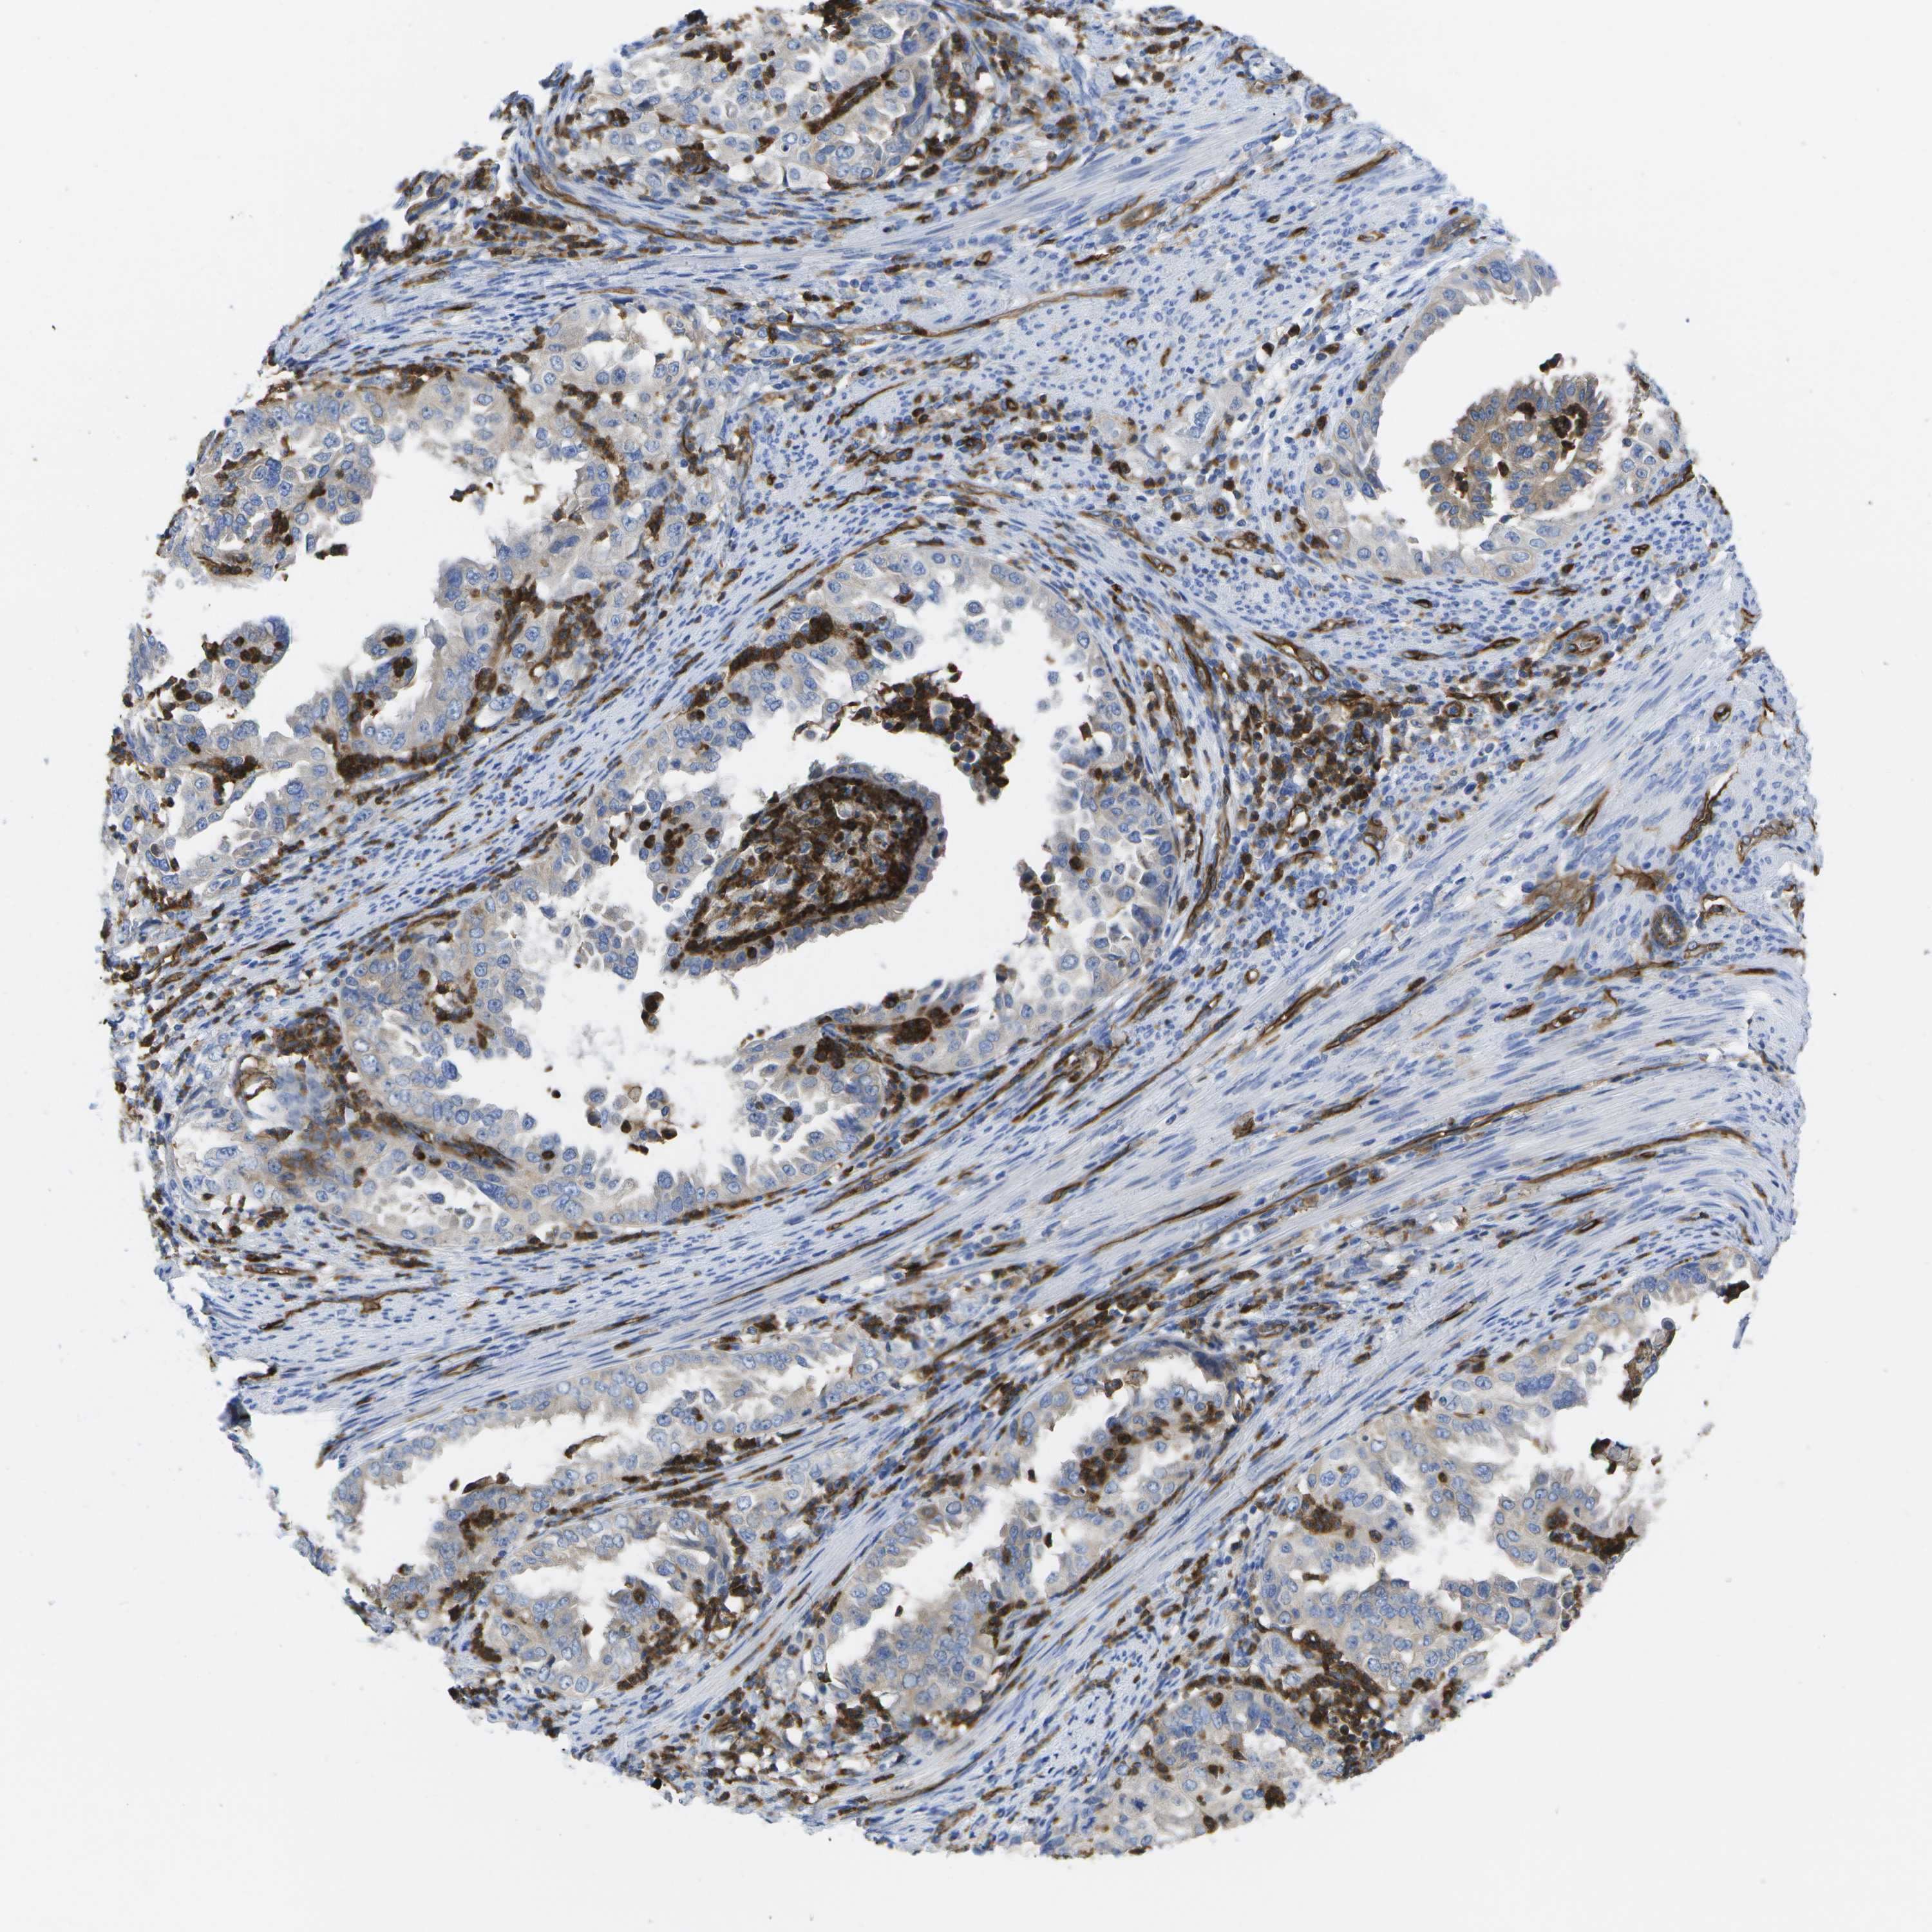

ENDOMETRIAL CANCER - Protein expressioni

A mouse-over function shows sample information and annotation data. Click on an image to view it in a full screen mode. Samples can be filtered based on level of antibody staining by selecting one or several of the following categories: high, medium, low and not detected. The assay and annotation is described here.

Note that samples used for immunohistochemistry by the Human Protein Atlas do not correspond to samples in the TCGA dataset.

Antibody stainingi

Antibody staining in the annotated cell types in the current human tissue is reported as not detected, low, medium, or high, based on conventional immunohistochemistry profiling in selected tissues. This score is based on the combination of the staining intensity and fraction of stained cells.

Each image is clickable and will lead to virtual microscopy that enables deeper exploration of all samples and also displays staining intensity scores, fraction scores and subcellular localization as well as patient and tissue information for each sample.

Antibody HPA017071

Antibody HPA021945

Antibody CAB002510

Staining

High

Medium

Low

Not detected

Intensity

Strong

Moderate

Weak

Negative

Quantity

>75%

75%-25%

<25%

None

Location

Nuclear

Cytoplasmic/membranous

Cytoplasmic/membranous,nuclear